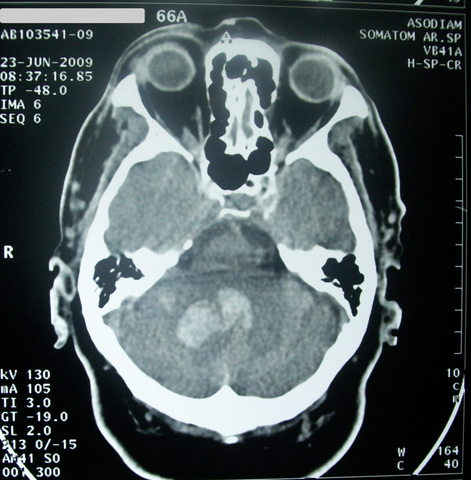

Pruebas y Exámenes

Examen físico para verificar si hay problemas con la visión, el movimiento, la sensibilidad, los reflejos, la comprensión y el habla.

Revisar si hay presión arterial alta.

Los exámenes para ayudar a localizar el accidente cerebro vascular es una angiografía de la cabeza para buscar un vaso sanguíneo que está bloqueado o sangrando, o una ecocardiografía para ver si el accidente cerebro vascular pudo haber sido causado por un coágulo sanguíneo proveniente del corazón.